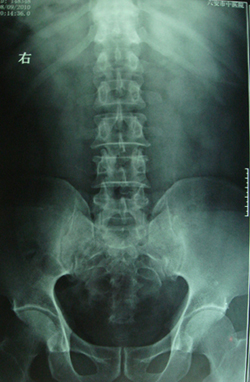

标题: CT28320:典型病例,男,56岁。无痛性血尿3月。 [打印本页]

典型病例,男,56岁。无痛性血尿3月。